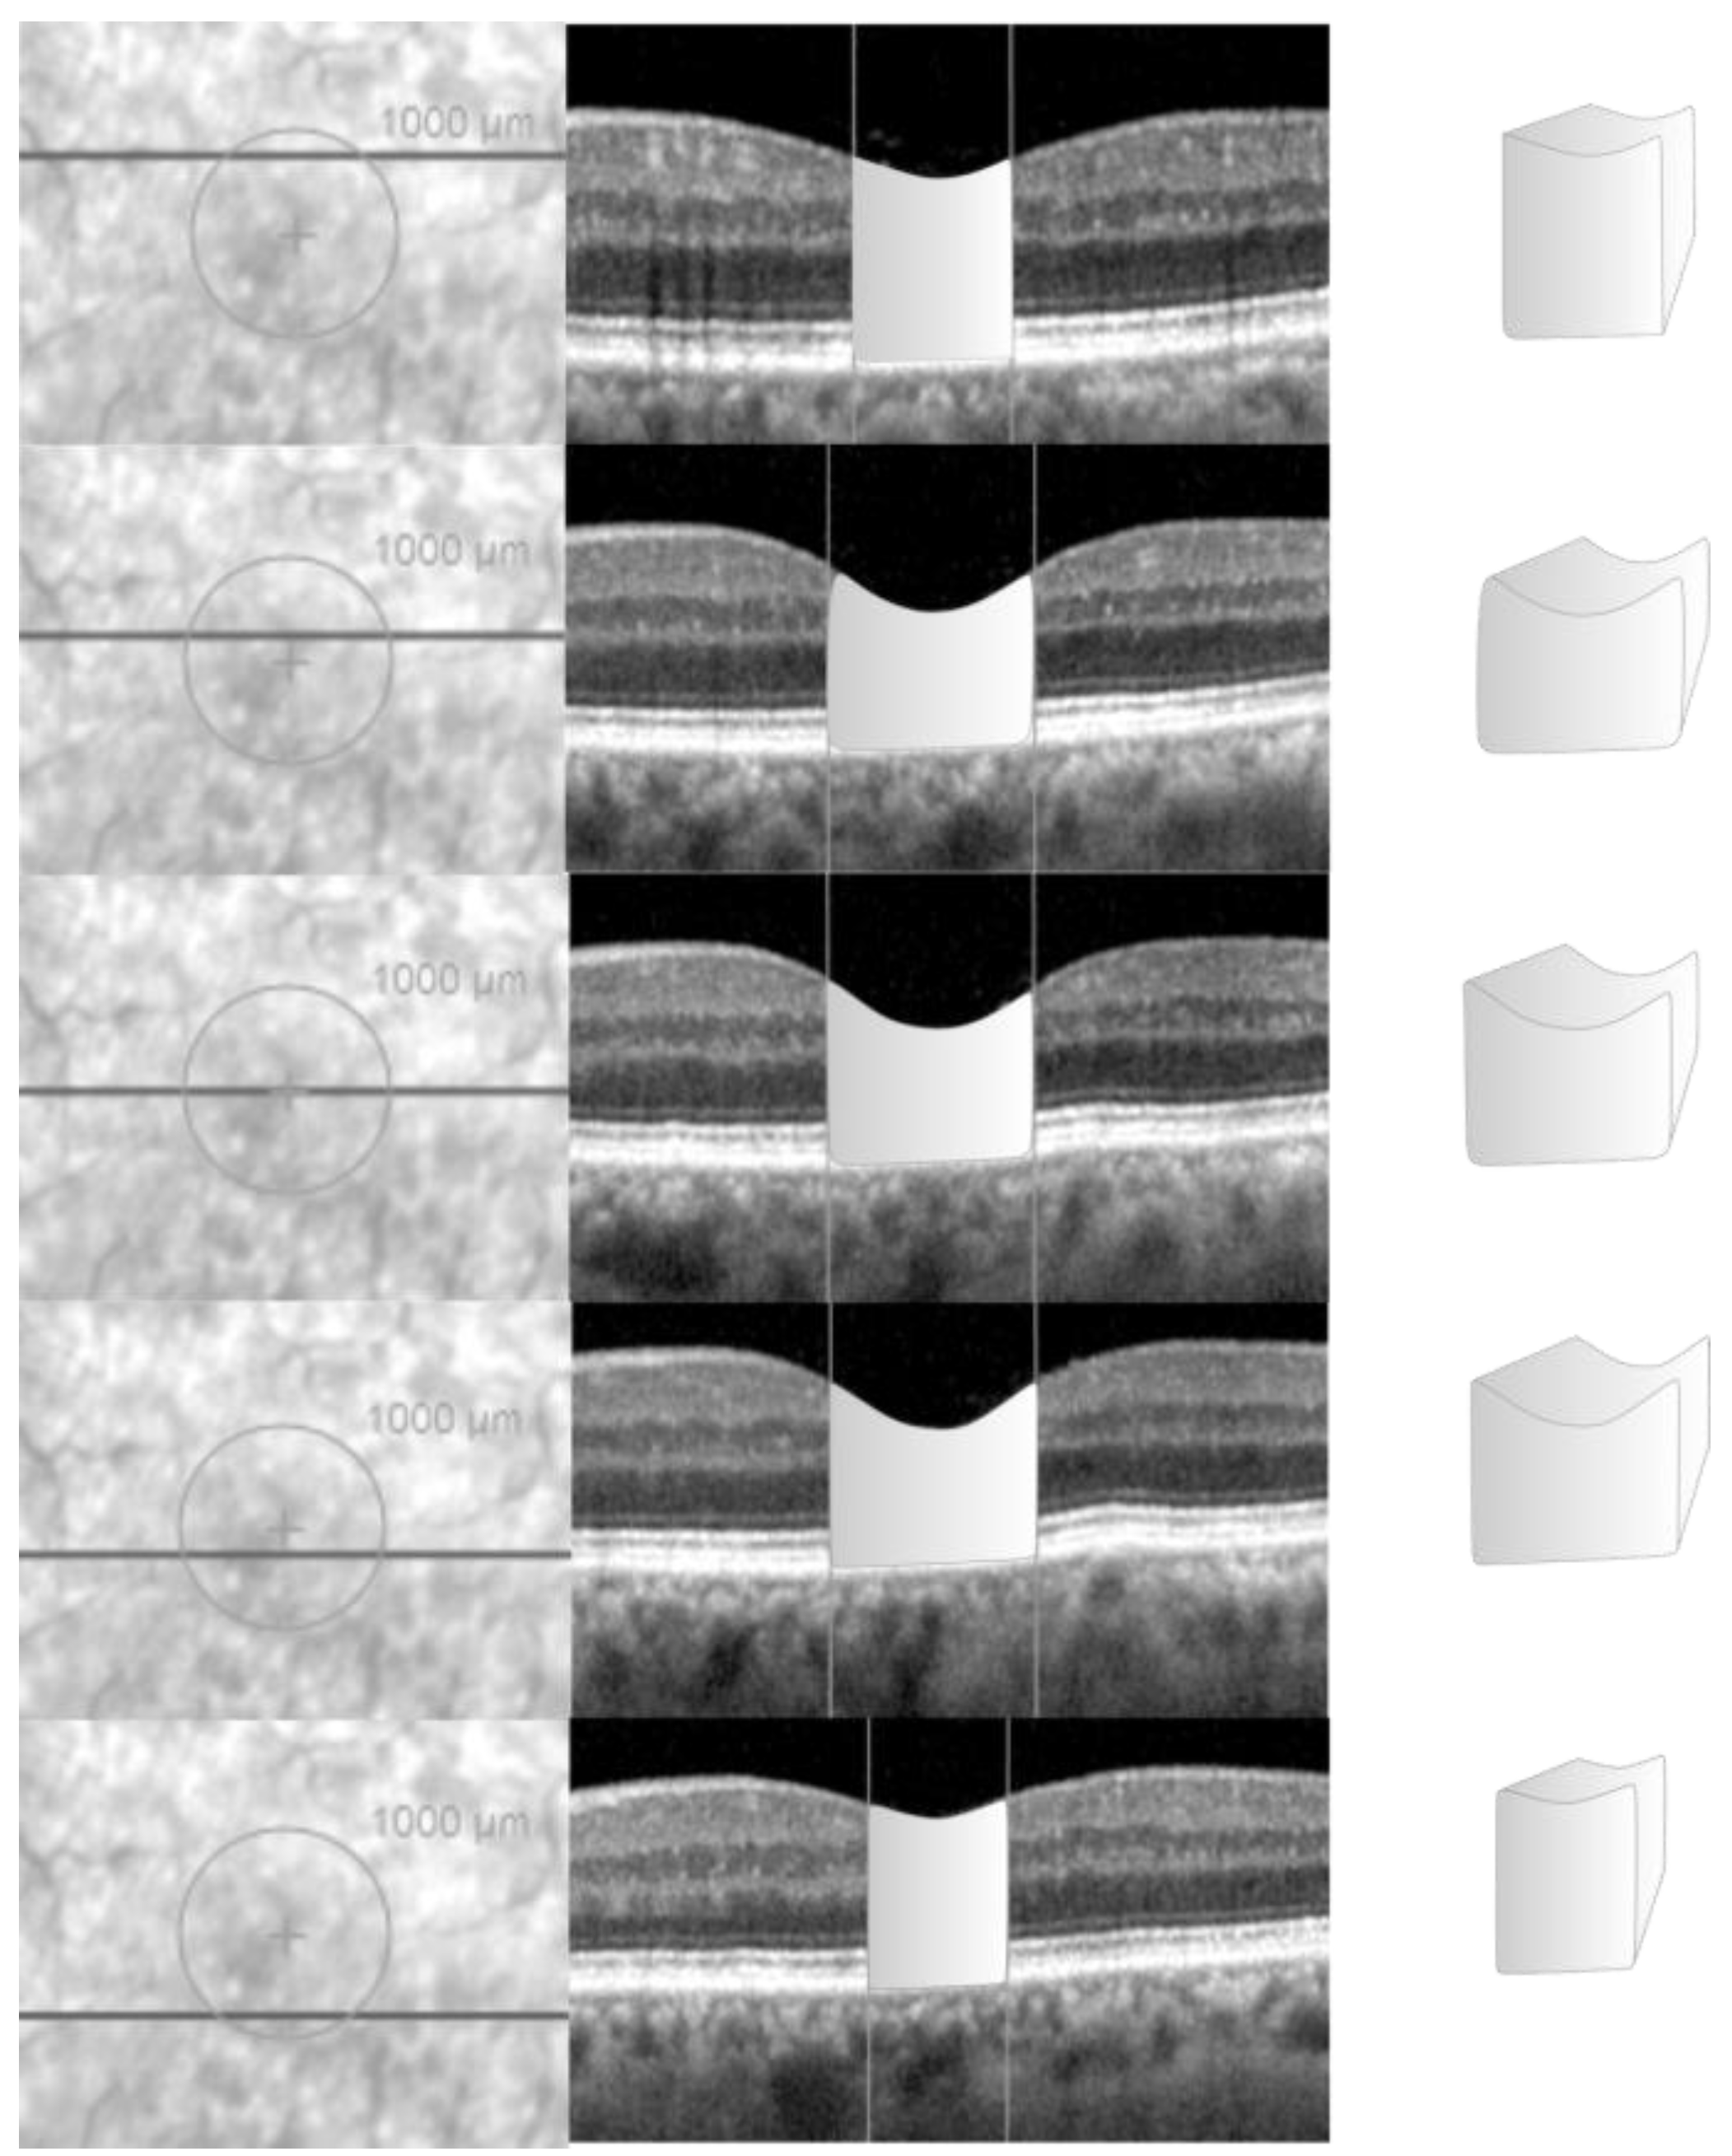

2.2. Data Acquisition in the NFP Group

2.3. Data Acquisition in the LMH Group